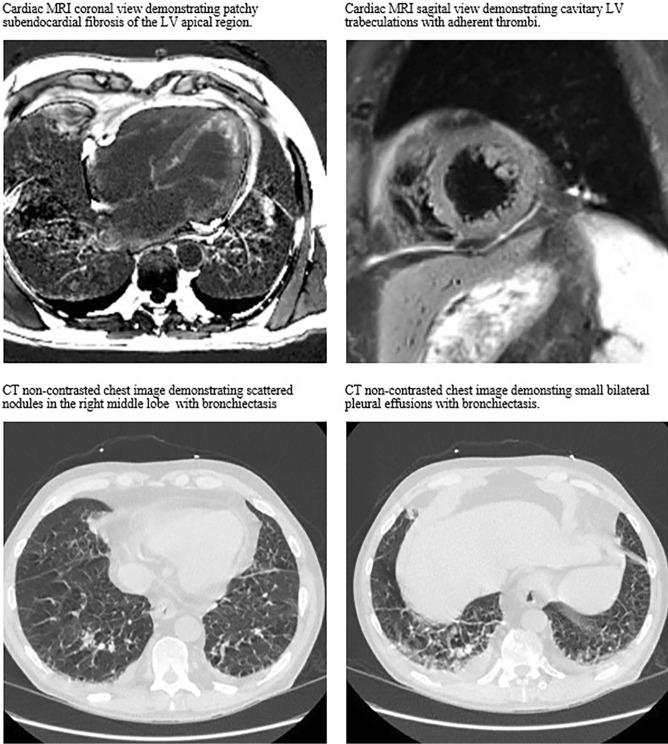

Treatments for eosinophilic granulomatosis with polyangiitis (eGPA) are rapidly evolving through using biologic therapies to modulate the Th2 inflammatory response via eosinophil inhibition. While IL-4, IL-5, IL-13, and IL-25 can all affect eosinophils, only IL-5 inhibition has demonstrated therapeutic benefit to-date. In this review, we report a clinical vignette of a patient with adult-onset asthma who developed severe manifestations of eGPA after switching from mepolizumab (an IL-5 inhibitor) to dupilumab (an inhibitor of IL-4 and IL-13). By understanding the role of IL-4, IL-5, and IL-13 in Th2-mediated vasculitis, we can start to understand how eGPA might respond differently to focused cytokine inhibition.

通过使用生物疗法来调节 Th2 炎症反应通过嗜酸性粒细胞抑制,嗜酸性肉芽肿性多血管炎(eGPA)的治疗方法正在迅速发展。虽然 IL-4、IL-5、IL-13 和 IL-25 均可影响嗜酸性粒细胞,但迄今为止只有 IL-5 抑制具有治疗益处。在本综述中,我们报告了一例成年起病哮喘患者的临床病例,该患者在从美泊利单抗(一种 IL-5 抑制剂)转换为度普利尤单抗(一种 IL-4 和 IL-13 抑制剂)后出现严重的 eGPA 表现。通过了解 IL-4、IL-5 和 IL-13 在 Th2 介导的血管炎中的作用,我们可以开始了解 eGPA 可能对靶向细胞因子抑制的反应有何不同。